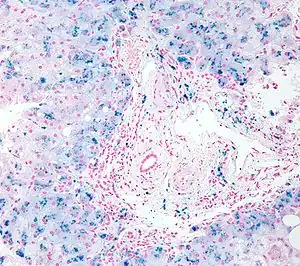

In histology, histopathology, and clinical pathology, Perls Prussian blue is a commonly used method to detect the presence of iron in tissue or cell samples.[1]: 235 [2][3][4] Perls Prussian Blue derives its name from the German pathologist Max Perls (1843–1881), who described the technique in 1867.[2] The method does not involve the application of a dye but rather causes the pigment Prussian blue to form directly within the tissue.[5] The method stains mostly iron in the ferric state which includes ferritin and hemosiderin, rather than iron in the ferrous state.[6]

Perls's method is used to indicate "non-heme" iron in tissues such as ferritin and hemosiderin,[6] the procedure does not stain iron that is bound to porphyrin forming heme such as hemoglobin and myoglobin.[2] The stain is an important histochemical stain used to demonstrate the distribution and amount of iron deposits in liver tissue, often in the form of a biopsy.[6][7] Perls's procedure may be used to identify excess iron deposits such as hemosiderin deposits (hemosiderosis) and in conditions such as hereditary hemochromatosis.[8] Perls Prussian blue is commonly used on bone marrow aspirates to indicate levels of iron storage[4] and may provide reliable evidence of iron deficiency.[7]

Perls did not publish a detailed procedure other than indicating a dilute potassium ferrocyanide solution was applied to the tissue followed by hydrochloric acid.[2] Ferric iron deposits in tissue (present mostly as ferric iron within the storage protein ferritin) then react with the soluble ferrocyanide in the stain to form the insoluble Prussian blue pigment (a complex hydrated ferric ferrocyanide substance). These deposits are then visualizable microscopically as blue or purple deposits.[9]